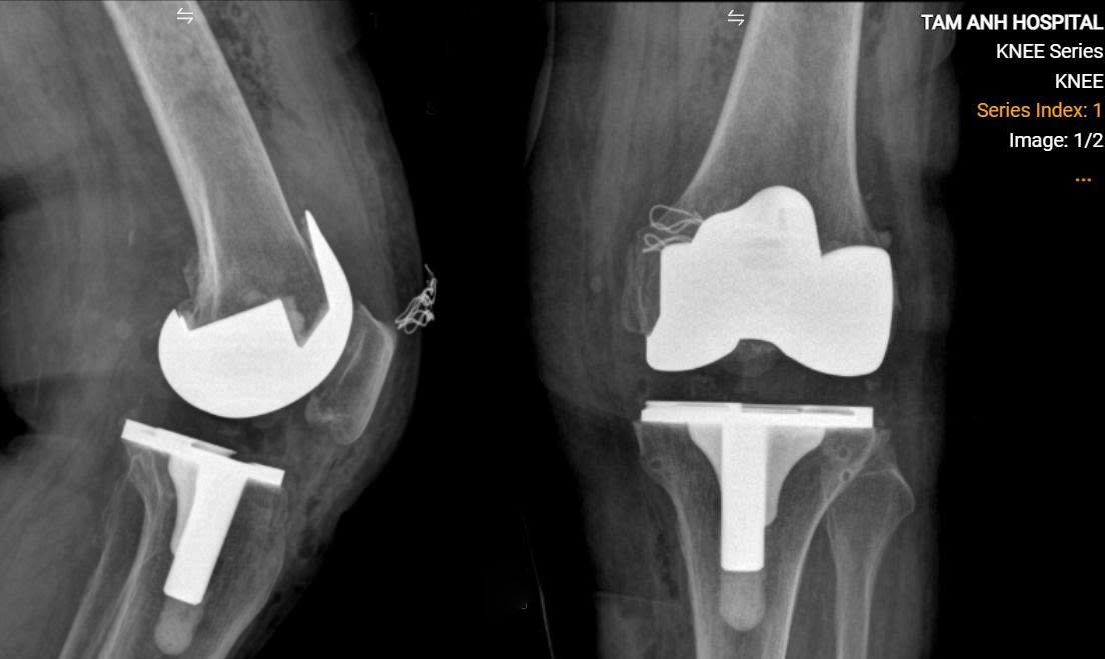

Ms. Tich's artificial knee joint. *Photo: Tam Anh General Hospital* |

Doctors performed a CT scan and created a 3D reconstruction of her knee. This allowed for precise measurements to select the appropriate joint type, determine optimal placement and orientation, and balance ligament tension. During the operation, Ms. Tich received spinal anesthesia combined with mild sedation for comfort, avoiding the complications of general anesthesia. Dr. Nghia incised to expose the knee joint, resected bone, and implanted the artificial joint. The surgery was completed in just over one hour.